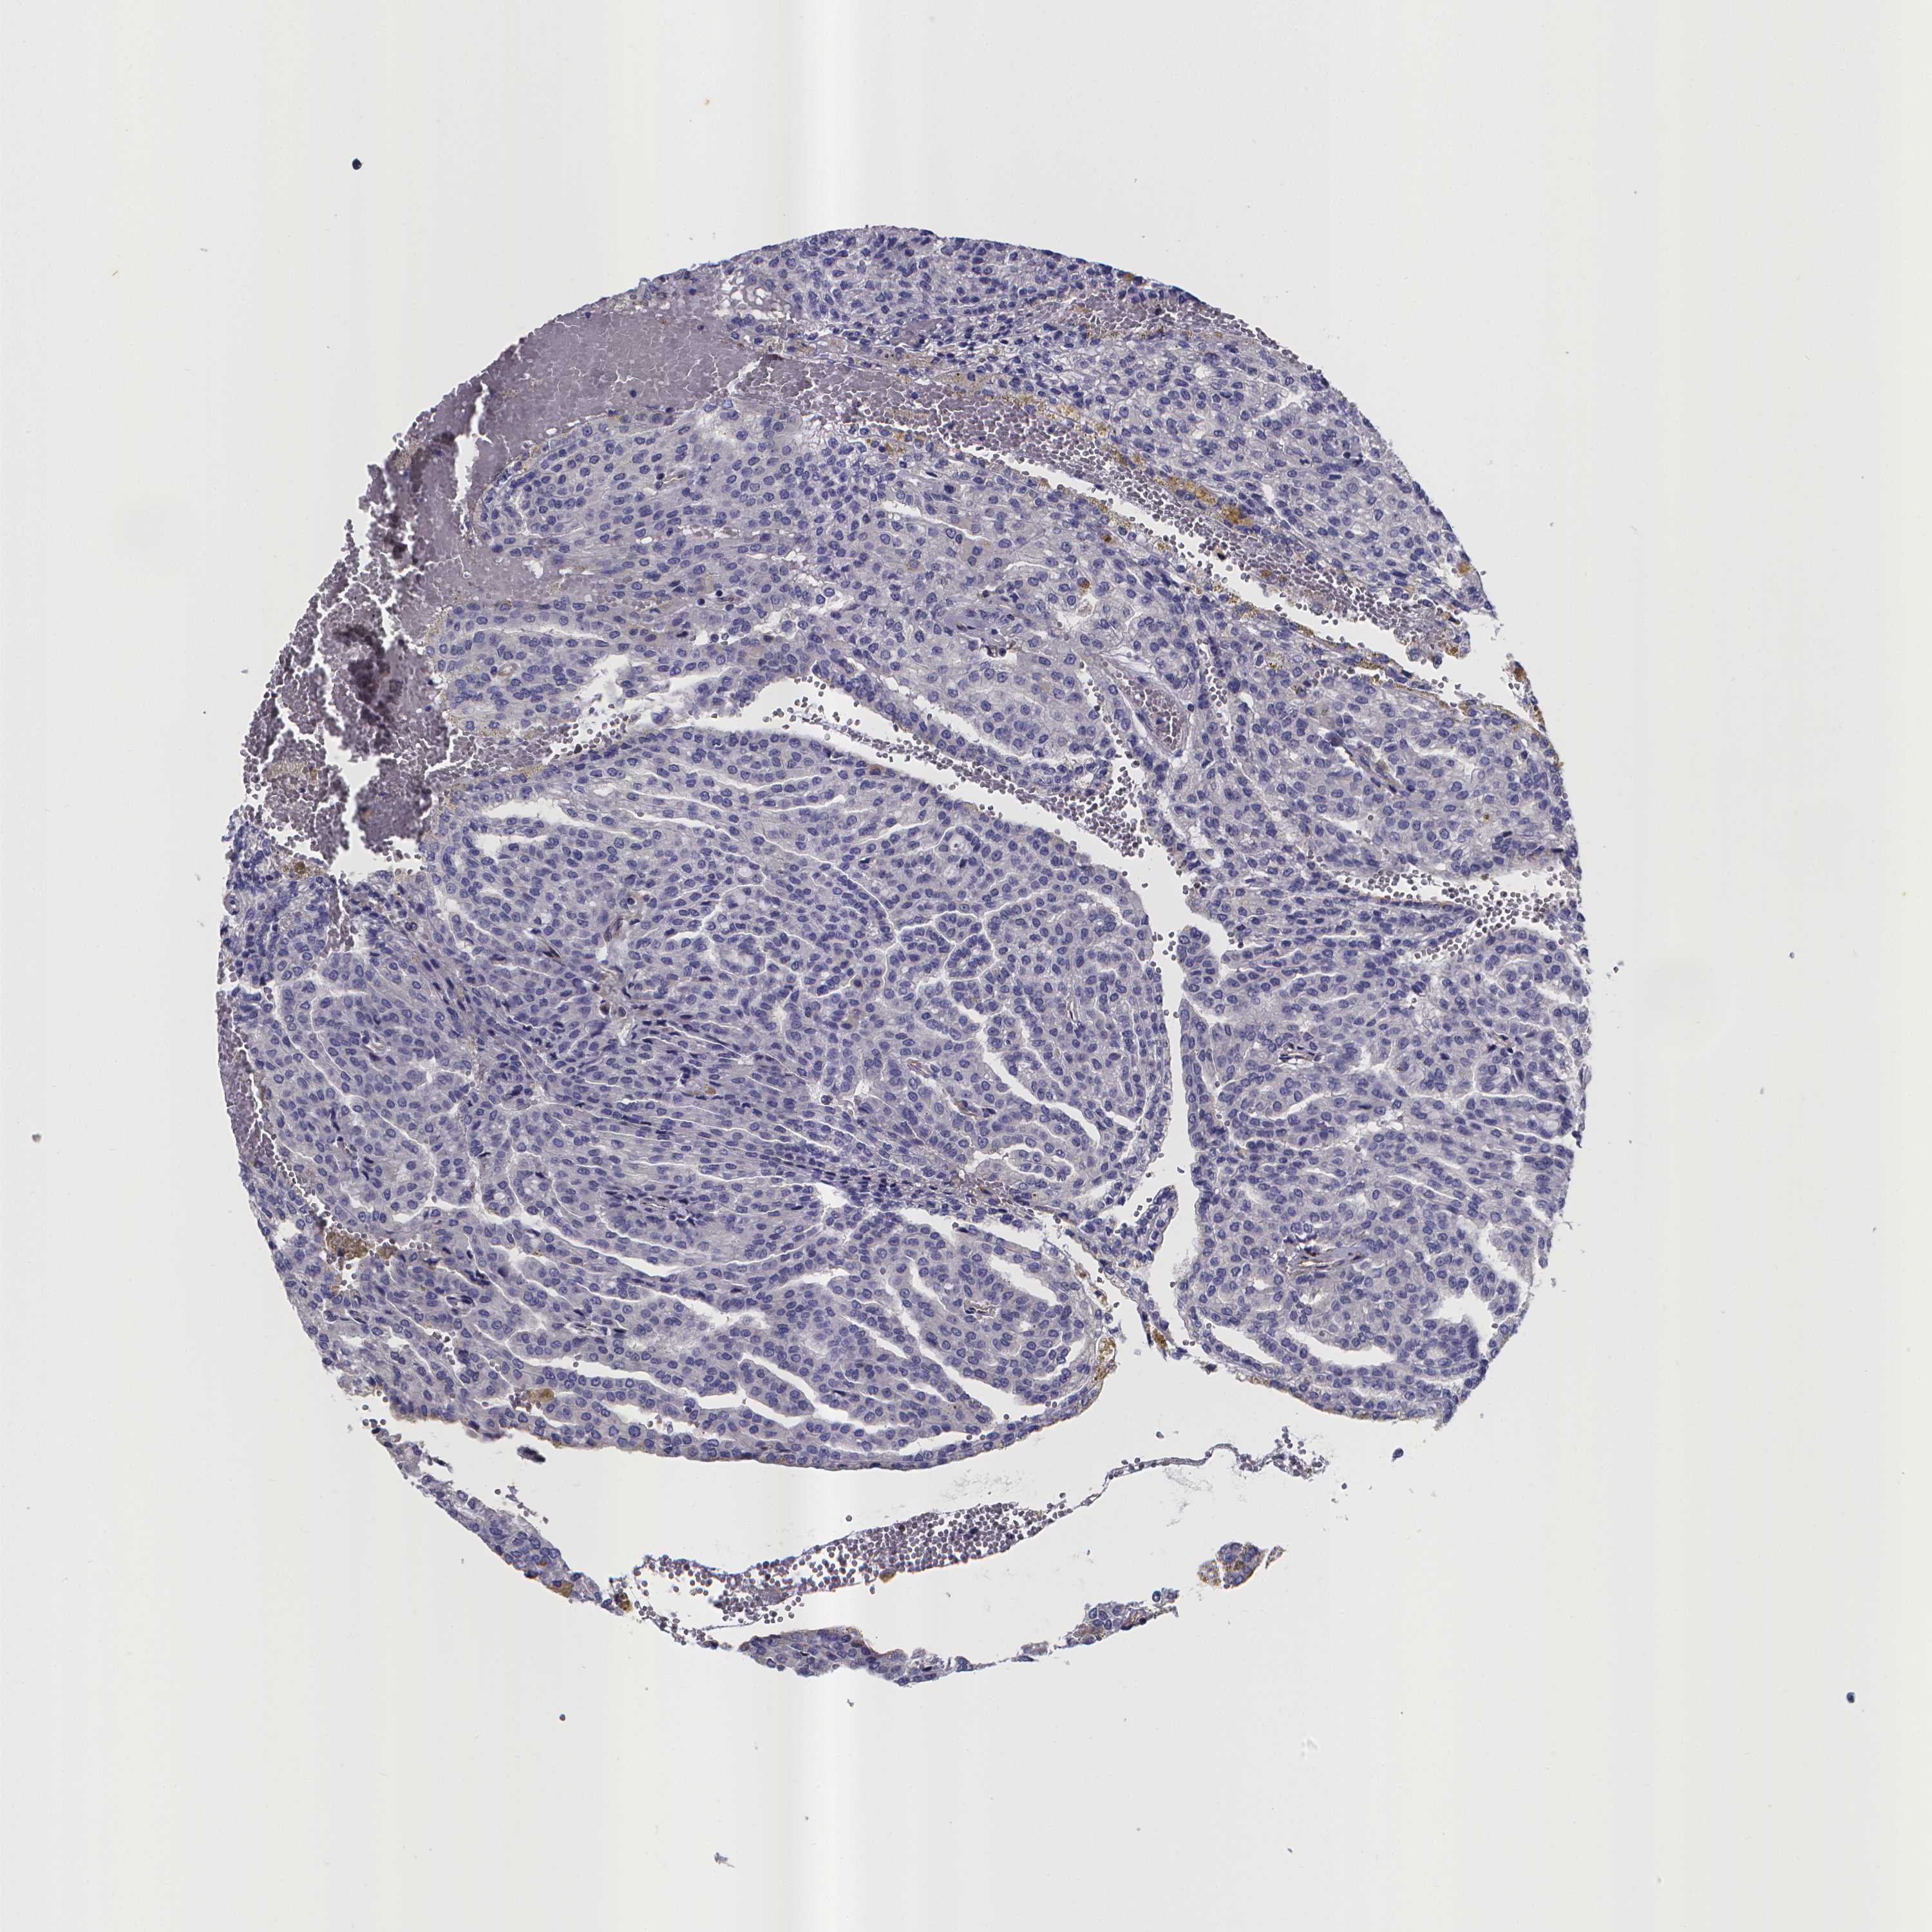

CANCER RENAL CANCER Show tissue menu

KICH TCGA KIRC TCGA KIRC VALIDATION KIRP TCGA PROTEIN RCC CPTAC PROTEIN EXPRESSION